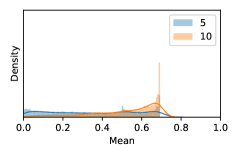

To model how different classifiers will respond to a given input , we assume that the prediction from classifier is sampled from a beta distribution that is characterized by two parameters by and . We further assume that is fixed to the same constant value for all ’s. Under this assumption, each input can be described by ( can be calculated since is fixed), easing further analysis. The Severity Level (SL) of the case represented by image can be characterized by the parameter . The larger the value of , the more severe the case of is. When and are close, the case is ambiguous as the distribution shifts towards being symmetric (i.e. signifying much disagreement among classifiers) rather than being one-sided (i.e. consensus among classifiers that is negative or positive). We provide a set of examples in Figure 2 and also Figure S.8 in the supplementary materials showing how the beta distribution can be used to capture diverse predictions given by an ensemble learner.

In contrast, the MC-dropout method showed the worst overall performance among the three, as it can be seen from the high ratios of SL0 examples among the uncertain negatives in Figure 4. The histograms in Figure 2 provides another perspective to look into the phenomenon, where a decent proportion of MC-dropout model’s predictions on SL0 inputs entailed low confidence (far from 0 or 1), which from another angle explained why MC-dropout was less specific in terms of lower FNP; many no-DR inputs (i.e. SL0) were erroneously assigned high uncertainty by MC-dropout models.

As discussed in Section 5.1 and Section 5.3 in the main paper, the mean metric and the stacking ensemble will have better performance in the precision (specificity) on the ambiguous data. Here, more detailed results are shown in Figures S.3 & S.6 and Table S.1. Figures S.3 & S.4 show the histograms of the uncertainty score for Kaggle-DR and Messidor-2 datasets that are the in-distribution (i.d.) dataset in our experiment and FigureS.5 & S.6 show the histograms for ImageNet and CIFAR-10 datasets, which is the o.o.d. datasets in our experiment. Each group of histograms contains results from the three evaluated ensemble methods (stacking ensemble, MC-dropout and TTA) and the three uncertainty metrics (mean, var and kl). Additional detailed results not displayed in Figure 4 can be found in Table S.1, which shows the proportion of the data of different SLs varies across different . For comparison, we also included in Table S.1 the results from single learners, and the proportions of data of different SLs (before any selection was made).